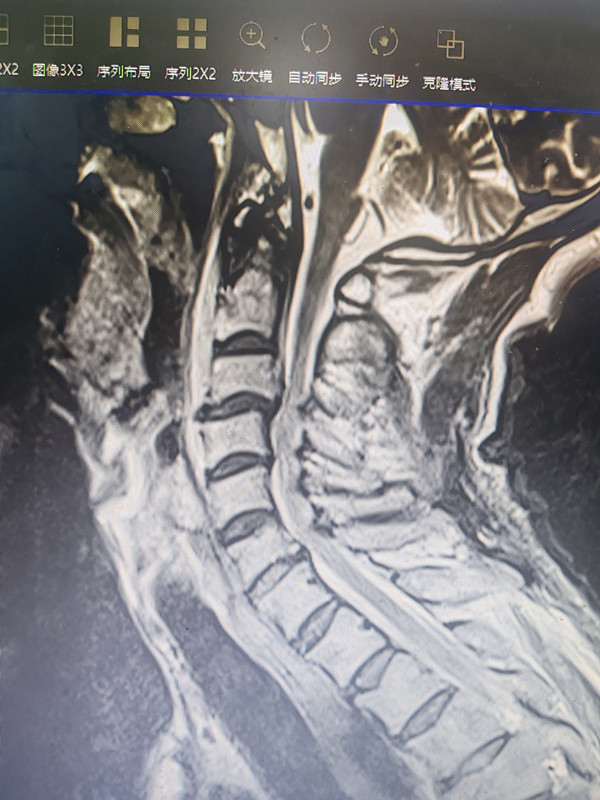

术前核磁检查脊髓严重受压情况

接受此次手术的是一位72岁高龄男性患者,因头颈部外伤导致颈椎过伸伤伴颈脊髓损伤、椎管狭窄伴后纵韧带钙化及急性完全性四肢瘫,病情危急且复杂。患者转入医院时,四肢肌力显著减退,肩部以下感觉麻木,多项神经反射未引出,若不及时手术干预,终身瘫痪的风险近在眼前。面对这一令众多医师望而却步的高难度诊疗挑战,刚刚进驻安医大附属安庆第一人民医院的荆珏华教授专家工作室及时落地龙山院区,成为患者的“救命稻草”。作为安徽省创伤骨科领域的学科带头人,荆珏华教授不仅在脊柱外科复杂疾病诊治方面造诣深厚,更有着博大的医者情怀。接到病例后,他放弃休息时间,连夜详细研判患者病情,结合颈椎 CT、MR 等检查结果反复推演,精准制定个性化手术方案。考虑到患者家庭的就医负担,荆教授不仅主动免收高额的专家会诊费,更全程无偿为患者实施手术,用实际行动践行“医者仁心”的初心,让患者在困境中感受到温暖。